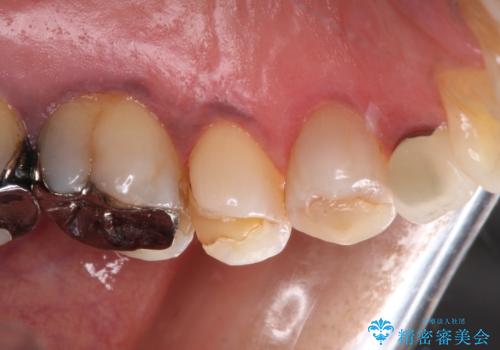

- 食事の度に痛みを感じるとのことで来院された患者様です。

診査の結果、既に歯の神経は失活していたおり、叩いたり触ったりしたときの痛みも確認されました。

まずは根管治療を行い、その後にオールセラミッククラウンにて補綴することとしました。

著しい八重歯であったそうで、一般的に抜歯を行う第一小臼歯ではなく八重歯を抜歯して矯正治療を行ったとのことでした。